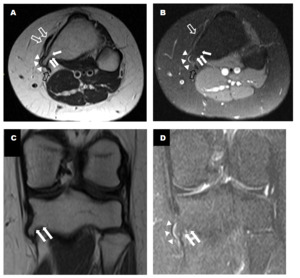

Further investigation with magnetic resonance imaging (MRI) revealed a small bony overgrowth, approximately 1 cm in size, along the medial aspect of the proximal tibial metaphysis. This overgrowth, identified as a pedunculated osteochondroma, showed cortical and medullary osseous continuity. No significant underlying bone marrow edema or pathological fracture was evident. Additionally, there was no cartilage cap thickening or aggressive features (Fig.2A, 2B, 2C, and 2D).

The anterior cruciate ligament (ACL) appeared thickened with intermediate signal intensity, indicative of a mild-to-moderate sprain, without a definitive tear. The posterior cruciate ligament (PCL), medial and lateral collateral ligaments, and menisci appeared intact. Notably, there was evidence of trochlear dysplasia. Additionally, there was mild displacement of the pes anserinus tendinous insertion without gross tendon tear or bursitis. The patellofemoral joint was grossly intact, with no significant joint effusion.

_axial_t2__(b)_axial_pdfs_(c)_coronal_t1__(d)_t2fs_mri_weighted_images_showed_proximal_.png)